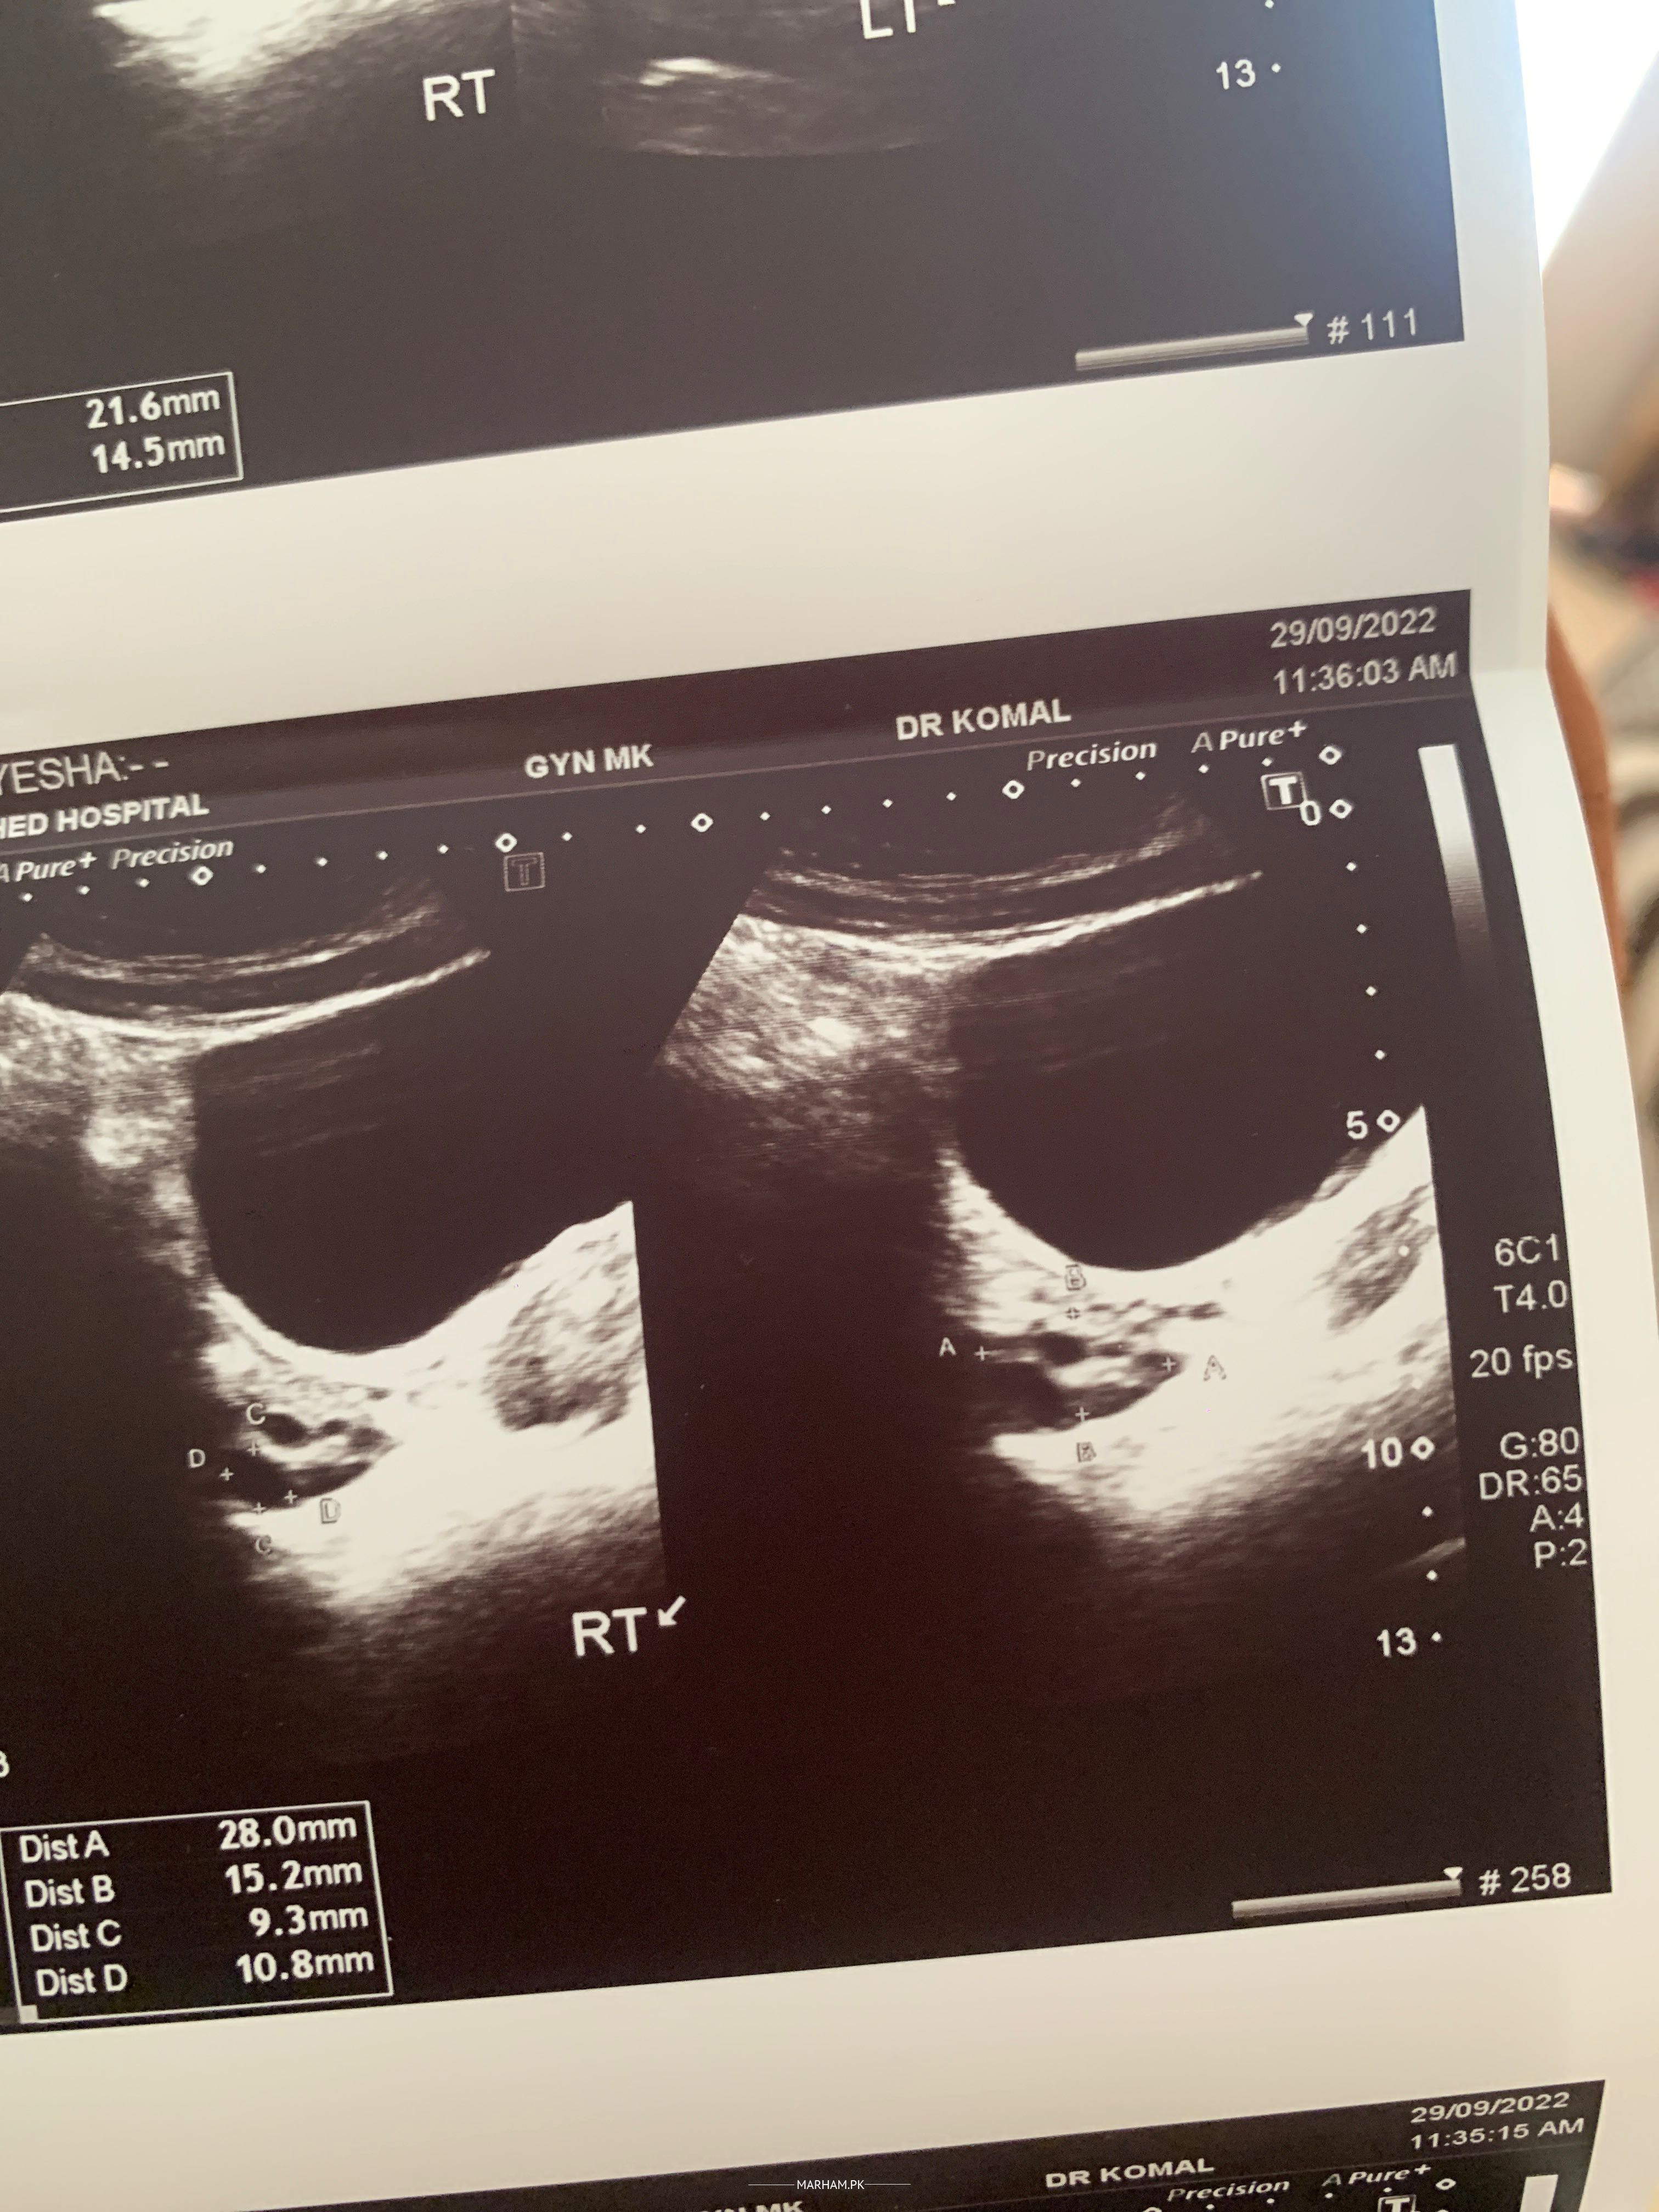

Kindly check my report and reply I’m in tension why is issue? Thankyou

Attach Photo here: